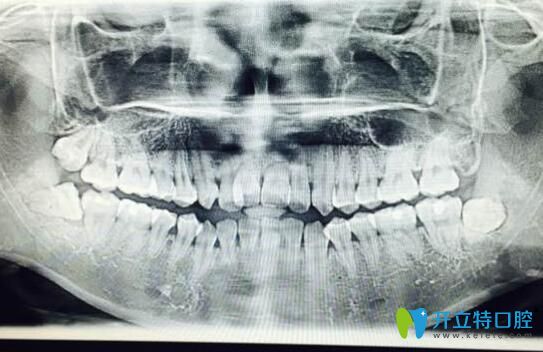

案例二:牙根短做正畸5個(gè)月自白

其實(shí)做正畸之前,我也非常擔(dān)心,但是變美的沖動大于一切,所以在認(rèn)真的篩選了和醫(yī)生之后,我開始了我的正畸之旅。

牙根短做正畸5個(gè)月自白

我已經(jīng)戴牙套5個(gè)月了,下個(gè)月還要打種植釘,而且迄今為止都比較好。

牙根短做了牙齒矯正

到現(xiàn)在我還是不后悔。沒有覺得牙齒有松動。為自己悄悄變美每天都很高興。